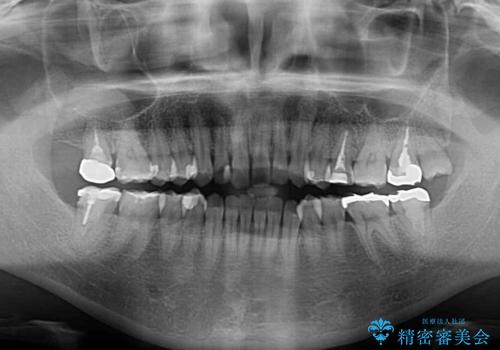

- 上下前歯の叢生を気にして来院された患者様です。

軽度な叢生であり、安価で短期間の治療を規模されていたため、インビザライン・モデレートを用いて矯正治療を行うこととしました。

インビザライン・モデレートは、製作できるアライナーの枚数に制限があるため、移動可能な量に限りがあるものの、インビザライン・ライトよりも枚数が多いため、幅広い症例に対応可能です。